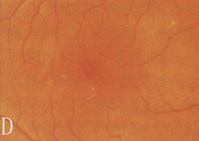

6、其他臟器併發症表現心血管病變如心力衰竭、心肌梗死。神經病變如周圍神經病變。累及自主神經時可出現神經源性膀胱。視網膜病變,糖尿病腎病嚴重時幾乎100%合併視網膜病變,但有嚴重視網膜病變者不一定有明顯的腎臟病變。當糖尿病腎病進展時,視網膜病變常加速惡化。

2.糖尿病視網膜病變和腎臟微血管病二者可同時存在。視網膜病變可繼發於糖尿病腎腎病以後,一般認為網膜病變的發生率高於腎微血管病變。因網膜病變易於觀察,而糖尿病腎腎病難於診斷,所以糖尿病人一旦出現網膜病變,要警惕腎病發生。